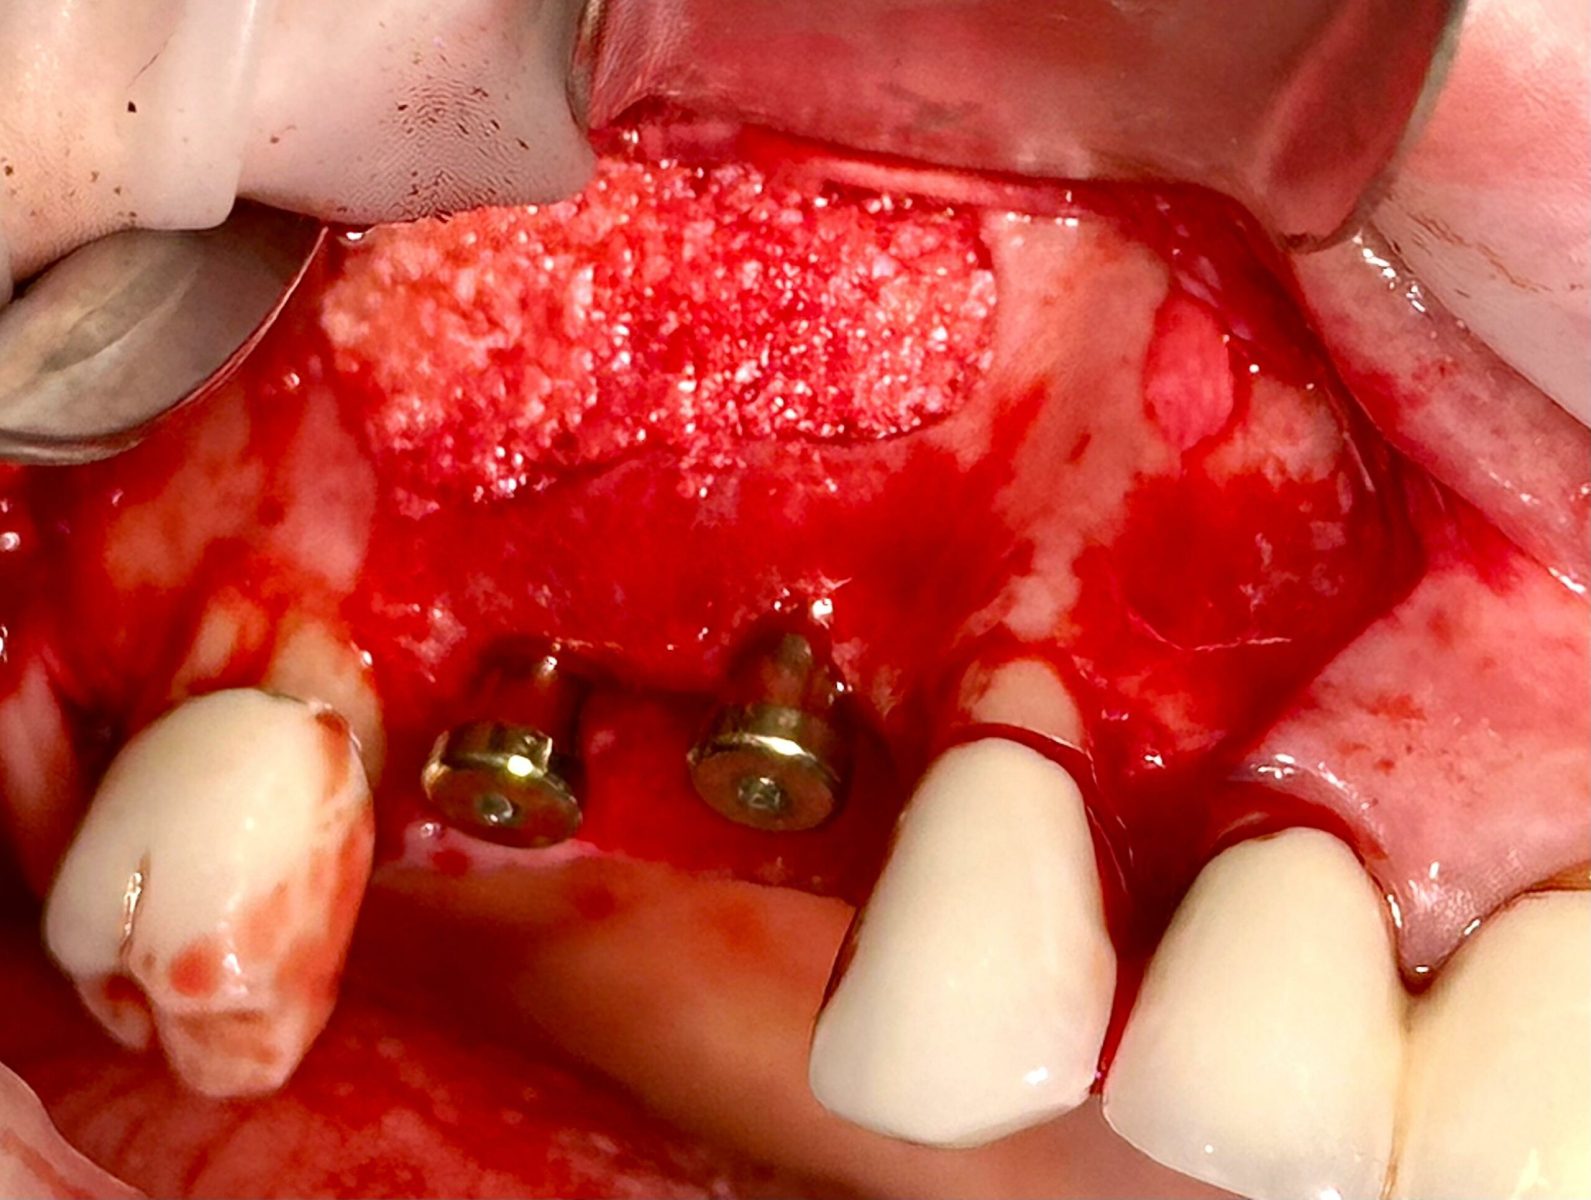

Implants placed using a digitally planned stackable surgical guide following alveolectomy, ensuring ideal positioning and a stable foundation for full-arch restoration.